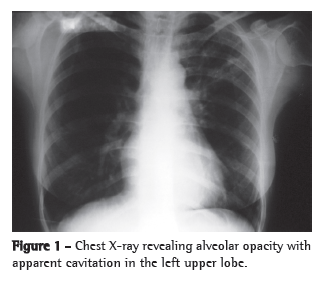

We report the case of a 41-year-old female homemaker from the city of Piracanjuba, located in the state of Goiás, Brazil. The patient had previously been diagnosed with arterial hypertension and had been using enalapril for several years. In addition, she had been diagnosed with RA more than ten years prior. During that period, she was treated with various therapeutic regimens for RA. She had been under treatment prednisone (5 mg/day) and methotrexate. Since she continued to have many joint symptoms, adalimumab was also prescribed. After two months of adalimumab treatment, the patient began to have low fever almost daily, as well as mild dry cough and mild asthenia. She sought medical attention at an emergency room in the city of Goiânia, also located in the state of Goiás, and was diagnosed with pneumonia after a chest X-ray (Figure 1). The patient used azithromycin (500 mg) for five days, in accordance with a prescription. The patient initially presented a slight improvement, but the dry cough and fever returned after the medication was discontinued. Two months later, since her clinical profile remained the same, she sought medical attention again, at which point a ten-day course of levofloxacin (500 mg/day) was prescribed. Again, she presented a slight improvement but the symptoms reappeared after the end of the course.

Another TST was performed, and the result was again negative (induration, 0 mm). Two consecutive sputum samples were smear-negative (Ziehl-Neelsen staining). The patient underwent bronchoscopy, which showed a whitish infiltrative lesion occluding 50% of the bronchial lumen of the left upper lobe as well as intense adjacent inflammatory reaction. The anatomopathological examination of the bronchial lesion revealed an extensive, chronic granulomatous inflammatory response with coagulative necrosis. There were no signs of malignancy. The bronchoalveolar lavage fluid tested positive for AFB in smear microscopy. The patient was diagnosed with pulmonary tuberculosis, and treatment with regimen I (rifampin/isoniazid/pyrazinamide) was instituted. She presented favorable evolution, showing improvement in the symptoms and in the radiological aspect thirty days later. The patient was discharged after six months of treatment, showing complete resolution of the respiratory symptoms and significant improvement in the chest X-ray results (Figure 4).